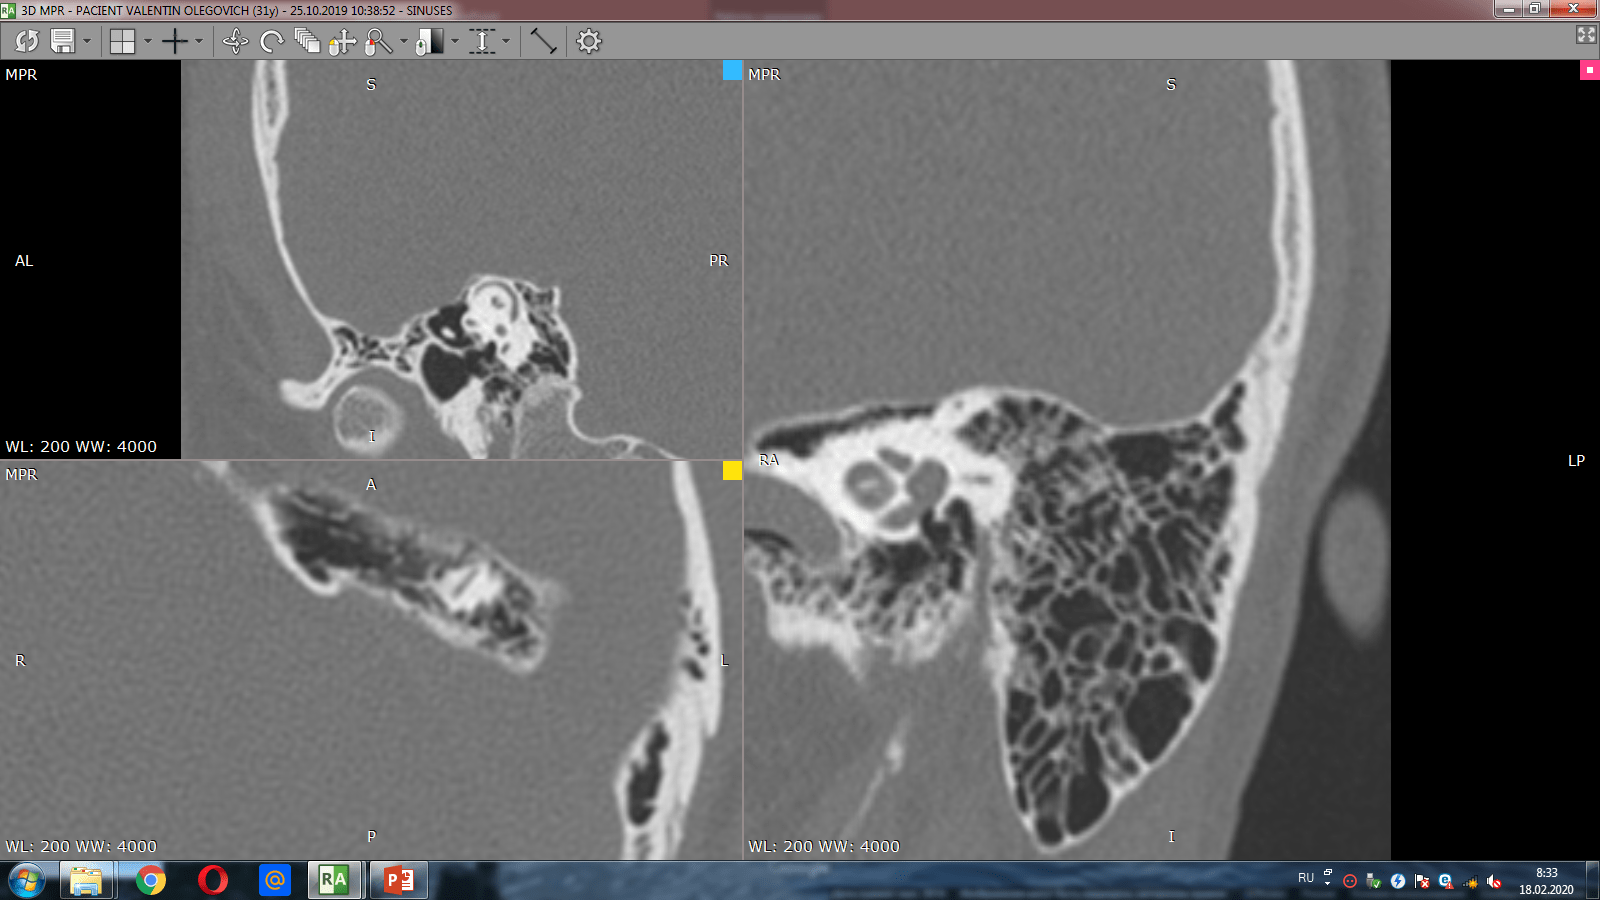

После консультации с врачами терапевтического профиля пациенту было рекомендовано обратиться за помощью к отоларингологу. По результатам компьютерной томографии была выявлена дегисценция костной стенки переднего (верхнего) полукружного канала.

КТ-диагностика